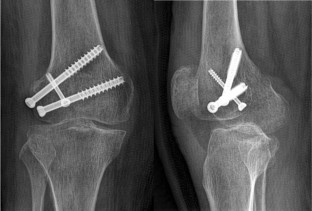

We treated eleven patients with Hoffa fracture using the new fixation method (fixation with one screw inserted from the femoral intercondylar notch and two screws inserted from the nonarticular lateral (or medial) surface of the fractured condylar fragment; the two sets of screws were crossed).

Fig. 1

Fig. 2